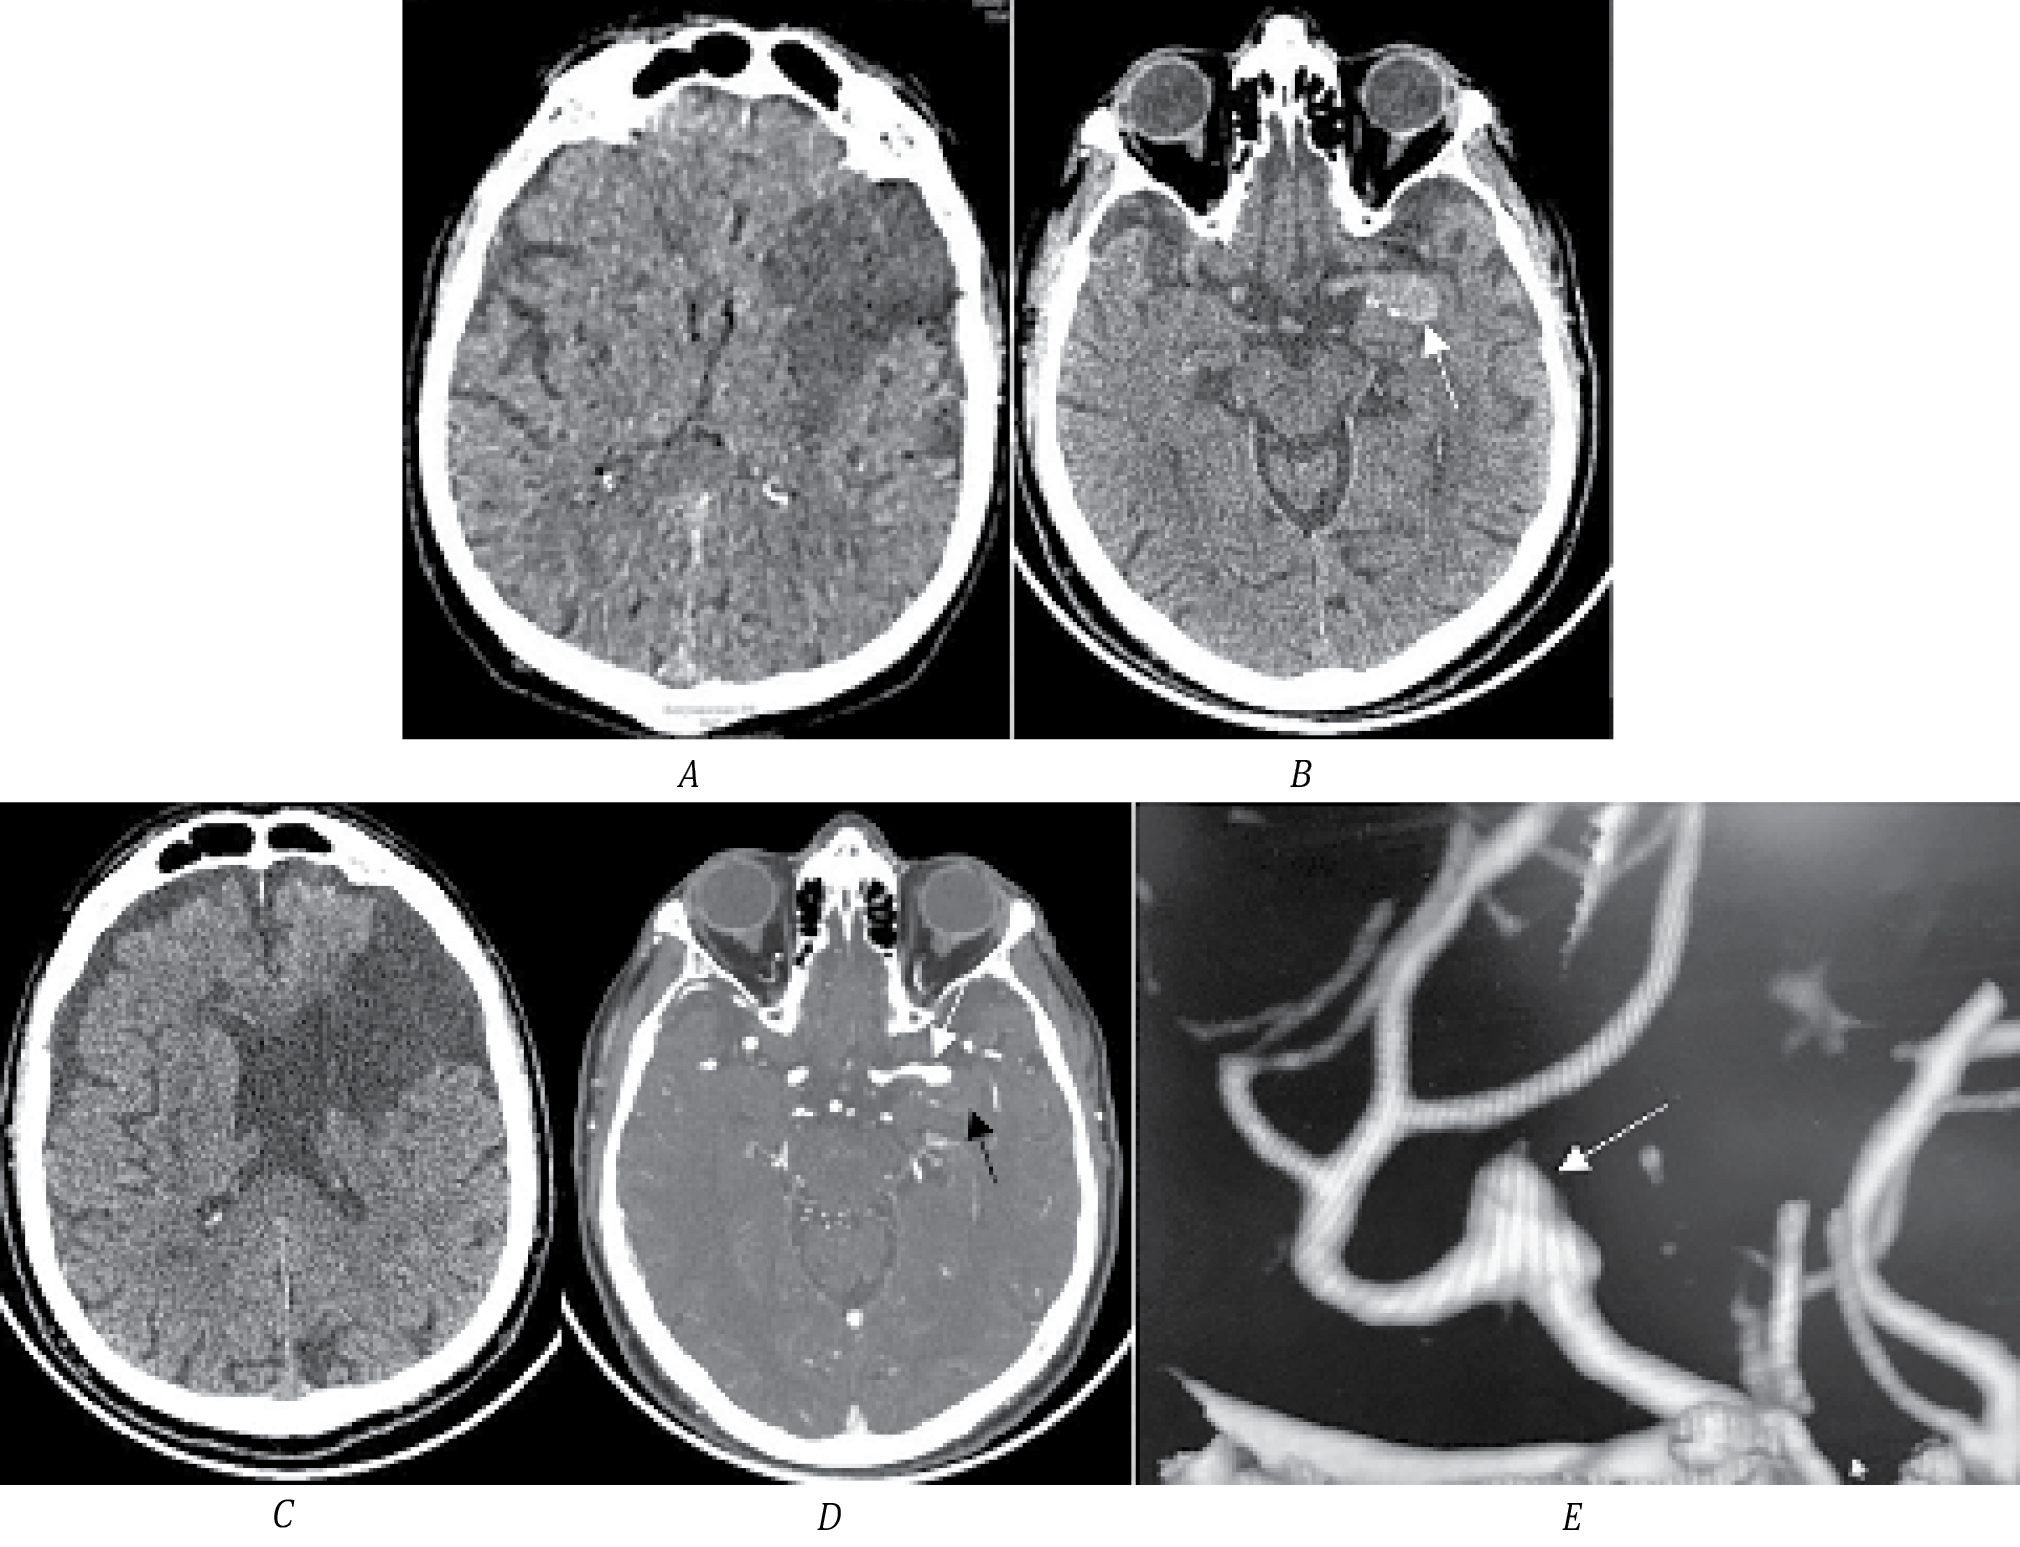

Пациентка Б., 57 лет, поступила в первичное сосудистое отделение с клиникой глубокого правостороннего гемипареза (до 3 баллов в руке и ноге). Неврологический дефицит тяжёлой степени (14 баллов по NIHSS). По данным МСКТ определена зона ишемии в области скорлупы, внутренней капсулы и головки хвостатого ядра слева (рис. 1, А). Обращает на себя внимание гиперденсный участок в области сильвиевой щели, который необходимо дифференцировать с кровоизлиянием и ТА (рис. 1, B). По МСКТ-ангиографии выявлена функционирующая часть ТА М1-сегмента СМА (рис. 1, C). Через 3 мес пациентка поступила на плановое оперативное лечение по поводу аневризмы СМА. В динамике на нативном МСКТ-исследовании сигнал от аневризмы стал изоденсным, по МСКТ-ангиографии определяется функционирующая часть аневризмы размером до 3,5 мм (рис. 1, D, E).

Рис. 1. МСКТ головного мозга пациентки Б.

А — острая ишемия в области головки хвостатого ядра, внутренней капсулы и скорлупы (стрелка); B — тромбированная часть аневризмы (стрелка); C — функционирующая часть аневризмы (белая стрелка), чёрной стрелкой указаны контуры тромбированной части; D — МСКТ пациентки через 3 мес после инсульта, стрелкой указана тромбированная часть аневризмы; E — 3D-реконструкция функционирующей части аневризмы (стрелка).

В остром периоде ИИ тромбированная часть аневризмы имела яркий (гиперденсный) сигнал, что указывает на наличие свежего тромба (рис. 1, B), а через 3 мес сигнал от тромба стал изоденсным (рис. 1, D). На основании зон ишемии в бассейне кровоснабжения лентикулостриарных ветвей и наличия свежего тромба в аневризме можно предположить, что причиной развития ишемии стал тромбоз стриарных ветвей СМА эмболом из мешка аневризмы. Других факторов риска ИИ у пациентки не выявлено. Выполнено микрохирургическое клипирование аневризмы. На операции определены небольшая функционирующая часть аневризмы и крупная тромбированная часть (13 мм). Мешок вскрыт, тромбы удалены, на сформировавшуюся шейку наложен постоянный клипс. Пациентка выписана с дооперационным функциональным статусом с оценкой по модифицированной шкале Рэнкина 3.